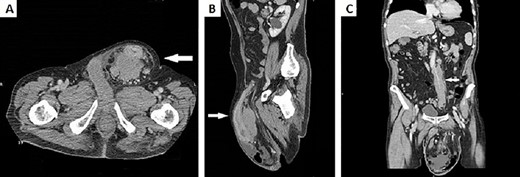

Physical examination revealed a hernia incarcerated in the left groin involving the scrotum. Computed tomography (CT) of the abdomen demonstrated a huge left inguinal hernia containing the sigmoid colon (Fig. 2A). Sigma’s walls appeared thickened for ~6 cm in length (Fig. 2B). No intestinal obstruction or peritoneal free air was detected. Massive adenopathy surrounding the inferior mesenteric artery (IMA) and enlarged para-aortic and pelvic lymph nodes were also present (Fig. 2C).

(A) CT scan of the abdomen demonstrated a huge left inguinal hernia containing distal descending colon and sigma (white arrow); (B) CT sagittal scan of the abdomen demonstrated sigma walls thickening inside left inguinal region (white arrow); (C) CT scan of the abdomen showed a bulky adenopathy encircling IMA just below its origin without vessel infiltration (white arrow).